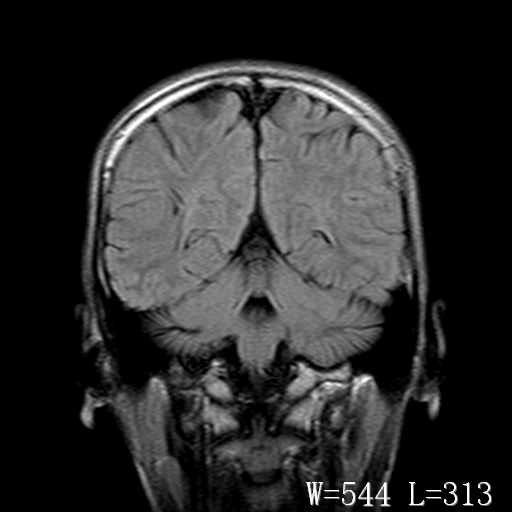

标题: PED3203:脑白质软化?

男,14岁,外伤入院。

双侧枕叶侧脑室旁对称性线状t2高信号 右侧斑点状t2高信号 增强一下可能有点用

支持右侧顶叶后部脑软化灶。

两顶枕区脑白质长t1、长t2信号,基本对称,应考虑脑白质病变,考虑髓鞘发育不良性疾病。且刚外伤,何来之脑软化灶?